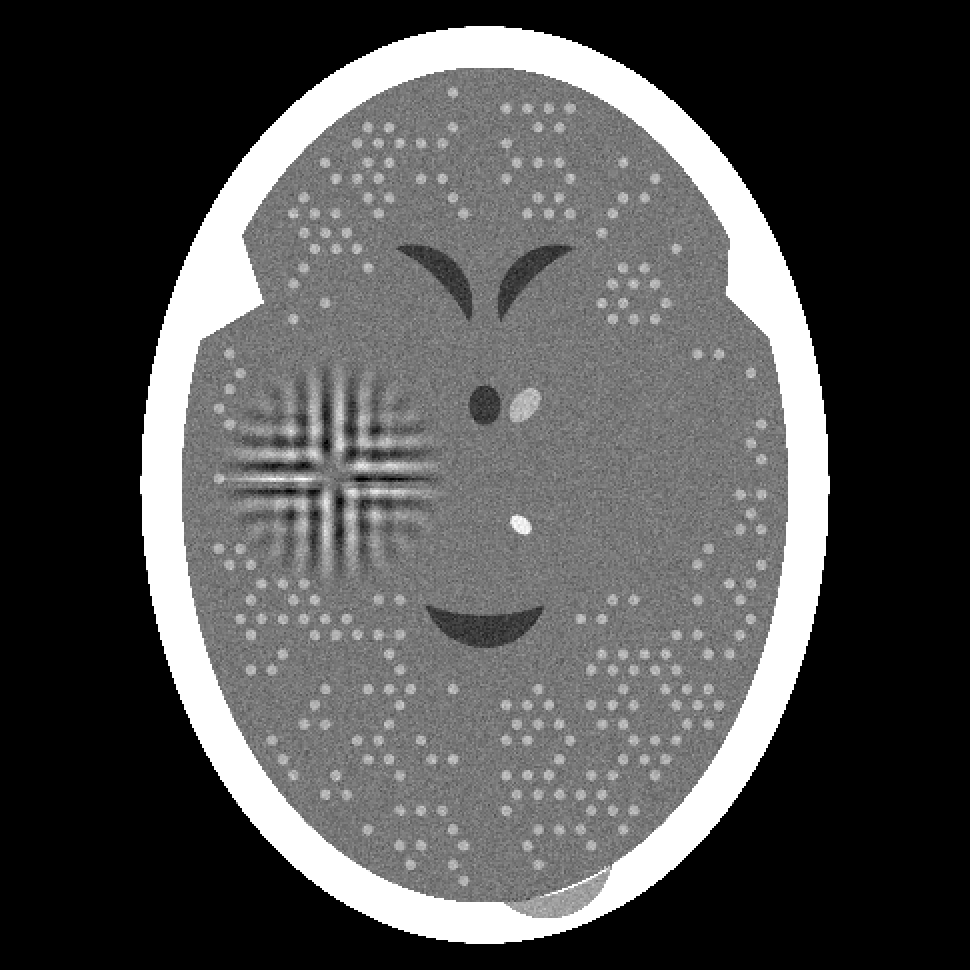

Figure 2: Reconstructions from 180 projections by (a) filtered back-projection, (b) the algorithm ART, (c) TV-Based Superiorized Version of ART, and (d) Shearlet-Based Superiorized Version of ART.

For this anecdotal experiment we use three different numbers of views (i.e., projections): 180, 360, and 720. We emphasize that, in the currently-described anecdotal experiment, there is only one phantom (which provides the ground truth); random generation of local inhomogeneities and of tumor locations is done only once and the same arrangement of local inhomogeneities and of tumor locations is used when generating the projection data for the three different numbers of views.

We present the visual results of the reconstructions produced by these algorithms when using 180, 360, and 720 projections in Figures 2, 3, and 4, respectively. We now give our impressions based on these visual results.

From the results for the single data set with 180 projections (Figure 2), we see that none of the four reconstruction algorithms produces an image in which the small tumors are easily locatable. Furthermore, the Shearlet-Based Superiorized Version of ART introduces high frequency artifacts in the brain near the skull and blurs the features inside the brain. In comparison, both filtered back-projection and ART (to a lesser extent) introduce artifacts in the form of streaks originating from interior bone edges. The image produced by TV-superiorized ART does not show significant high-frequency artifacts, the only one of the four, but the image is blurred.